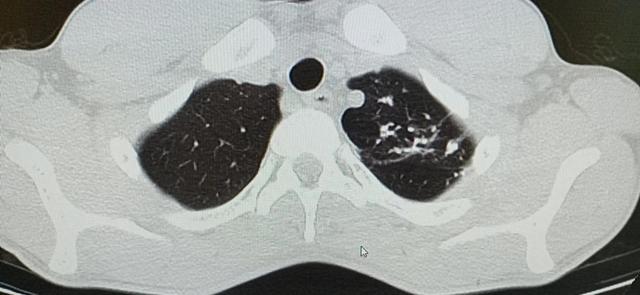

急性粟粒型肺结核 CT肺窗,两肺可见分布均匀、大小均匀、密度均匀的粟粒状影,边界清晰

(1)X线:初期仅见肺纹理增多,约在两周才出现典型粟粒样结节。表现为广泛均匀分布于两肺的粟粒大小的结节状密度增高影。其特点为病灶分布均匀、大小均匀和密度均匀,即所谓“三均匀”表现。由于病灶数量多且分布密集,两肺野可呈磨玻璃样改变。分布密集的粟粒样结核可将肺纹理遮盖,使正常的肺纹理不易辨认。大小一致的粟粒样致密影,其直径1~2mm。境界较清楚,若为渗出性病灶则其边缘不清。晚期粟粒状密度增高影常有融合的倾向。

(2)CT:易显示粟粒结节,尤其HRCT 可清晰显示弥漫分布的粟粒性病灶,更加典型地显示粟粒结节分布均匀、大小均匀和密度均匀的“三均匀”的特点。